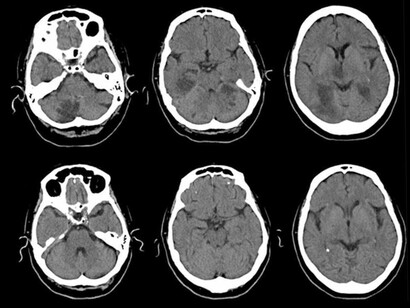

- Parkinsonismo vascular: es la consecuencia de múltiples ictus pequeños que pueden afectar el equilibrio, la marcha y la memoria, mostrando síntomas similares a la EP.

Es probable que también ordene análisis de sangre para detectar posibles causas subyacentes, como problemas de tiroides o hígado. Así como pruebas de neuroimagen (TAC o escáner, resonancia magnética nuclear y pruebas de medicina nuclear). Las pruebas de medicina nuclear rastrean el movimiento de dopamina en el cerebro y son conocidas de múltiples formas como SPECT, Datascan o DaT-SPECT y tomogammagrafía. La prueba utiliza marcadores radioactivos diseñados para rastrear la dopamina en el cerebro. Esto le permite al médico observar la liberación de este neurotransmisor en el cerebro de una persona e identificar las áreas cerebrales que la reciben o no atendiendo al brillo de dichas zonas.